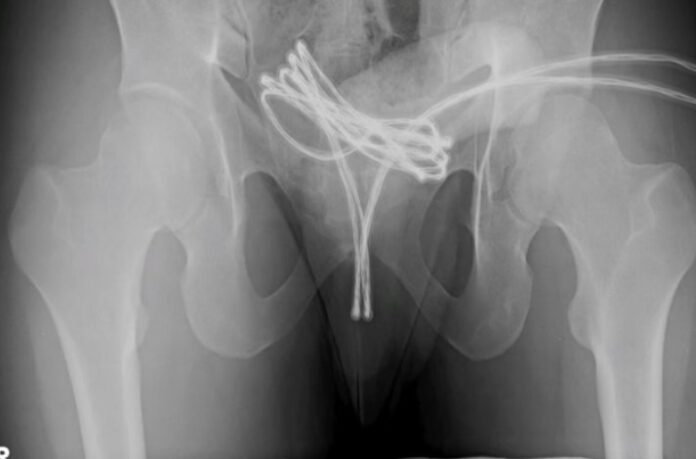

Exames mostraram que o cabo havia alcançado a bexiga, impossibilitando a remoção simples. Foi necessário realizar uma cirurgia sob anestesia geral com auxílio de uma câmera para retirar o objeto sem causar danos maiores.